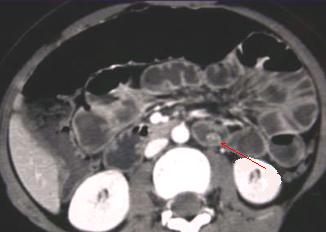

Petit lipome de

l'intestin ( fleche rouge ) . Aspect TDM

arrondie pedicule a hypo-dense endoluminale de

intestin a la region fosse iliaque gauche |